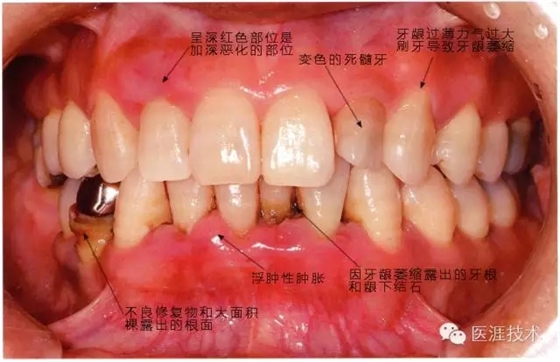

56歲牙周炎男性的臨床照片

正在服用高血壓藥中的56歲男性。菌斑控制得不好。通過牙周探診,全頜有4~6mm的牙周袋,在X光片中可以看到全頜中度牙槽骨吸收,磨牙處一個地方是重度牙槽骨吸收。通過比較牙周病進(jìn)展?fàn)顟B(tài),邊緣部有大范圍浮腫(發(fā)紅、腫脹),和纖維性肥厚。這也可能是服用中的降壓藥的副作用導(dǎo)致的。因為牙齦、牙槽骨比較厚,牙齦呈架子狀。